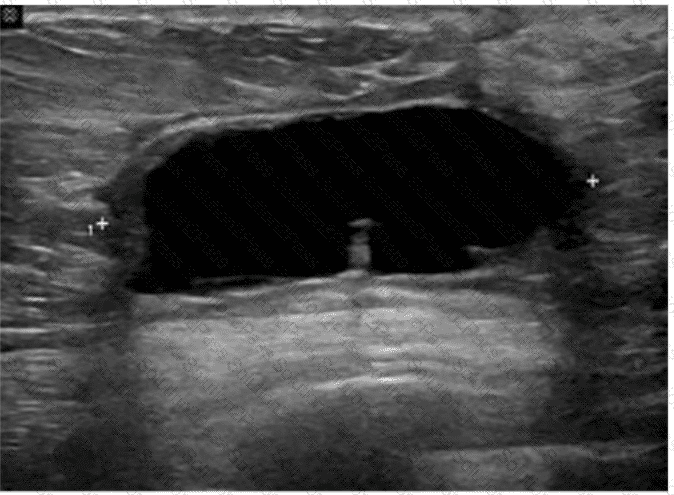

Which condition of the transplant kidney is indicated by the arrows on these images?